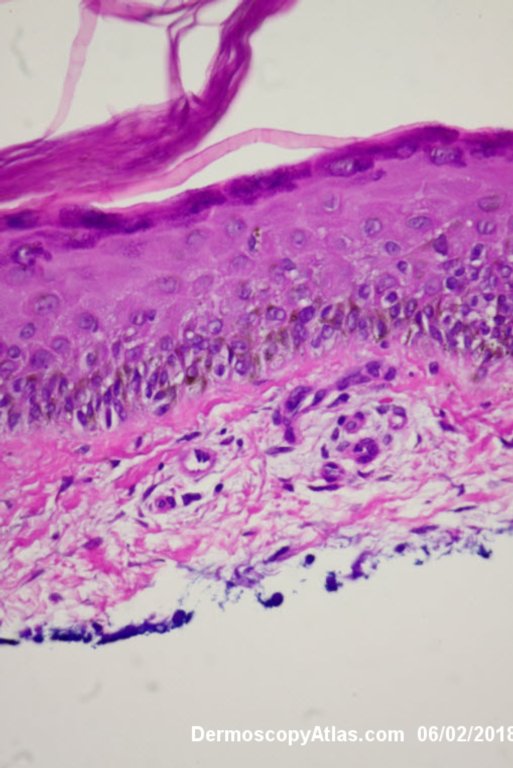

Diagnosis: Melanoma invasive

Lady in her early 80s who presented with this lesion on her ankle. The pigmented area had been there for some time but the pink area was bleeding and new. Shave of surrounding area and a punch biopsy of the new pink area showed mainly surrounding in situ melanoma with invasive melanoma in the pink area 1.8 mm thick. Having a 2cms margin excision of the whole area and a graft.